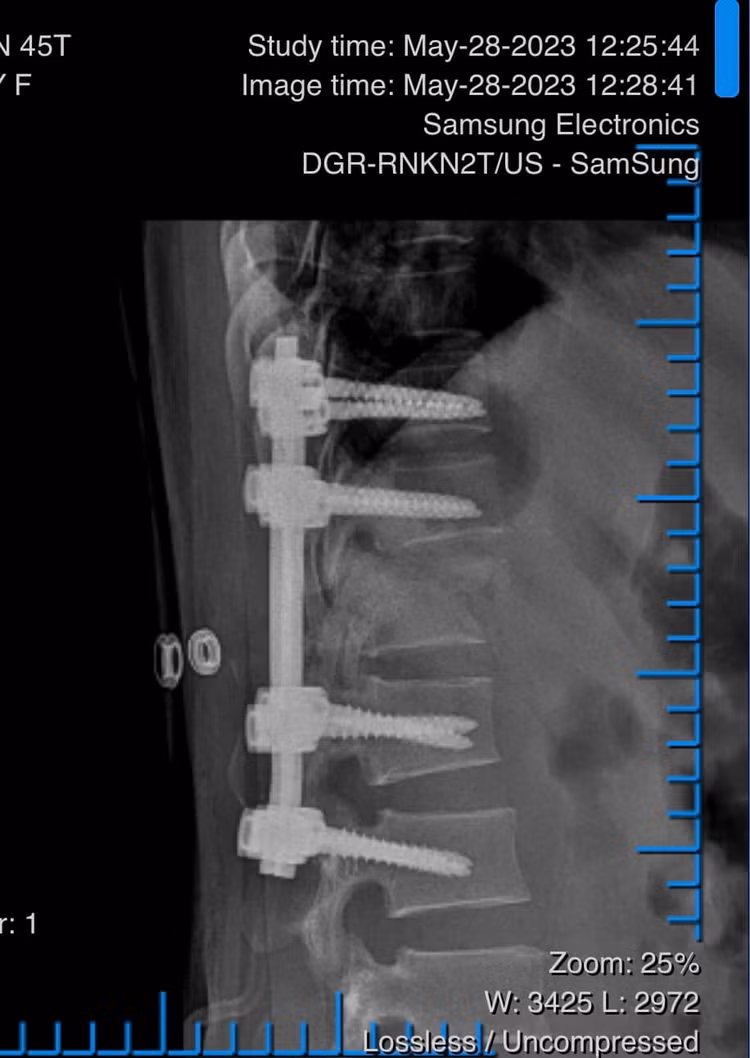

Trong mổ, bệnh nhân được kiểm tra cẩn trọng các tổn thương, tuy nhiên khi bị ngã, tủy sống của bệnh nhân đã bị đứt hoàn toàn, không thể cứu vãn được, chỉ còn có thể nắn chỉnh cột sống về vị trí giải phẫu (thẳng trục) bắt nẹp vít cố định vững chắc, để sau này bệnh nhân có thể ngồi được và di chuyển bằng xe lăn.

![]() |

| Phẫu thuật nẹp vít cột sống cho bệnh nhân |